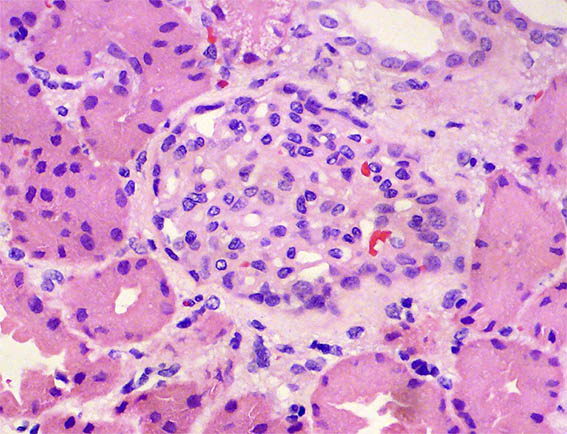

Con diagnóstico de síndrome nefrótico, se hace biopsia renal. Observe las imágenes.

Figura 3.

H&E, X400.